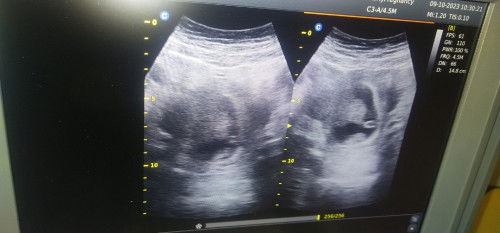

Bun bantu jawab yh perkiraan saya sekarang tuh udh masuk 9minggu Bun tapi pas di USG katanya baru 5m

Bun maaf bisa bantu jawab perkiraan saya sekarang sudah masuk 9 Minggu tapi pas di USG katanya baru jalan 5minggu karena blm ada janin nya ikutin perkiraan yg mana yah Bun